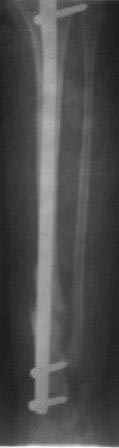

Уважаемые коллеги! помогите советом! Мальчик 2000 г.р. В 2007г получил

перелом н/з костей правой голени,

в районе лечили гипсом 6 месяцев, сращения нет, в обл.центре КДО

аппаратом Илизарова - 3 месяца, после повторная деформация, в НИИТО КДО

аппаратом Илизарова -7 месяцев, перелом якобы сросся, но после снятия

аппарата через 2 недели после незначительной травмы повторный перелом. И

было произведена после рассверливания канала БИОС плечевым стержнем,но

стержень пошел по мед.стенке дистального отломка поэтому остался

некоторый вальгус(операция без ЭОП) ребенок через неделю начал

самостоятельно ходить, клинически деформации нет, все обрадовались,

выписали, повторно приехали только ч-з 1,5 года вот с такой деформацией,

но ребенок ходит в школу, бегает, незначительно хромает, родители

требуют исправить деформацию.